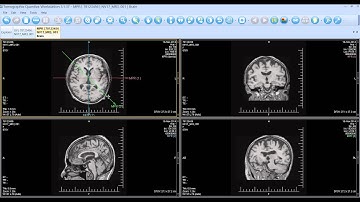

MPR-Reconstruction | PACScenter Tutorial